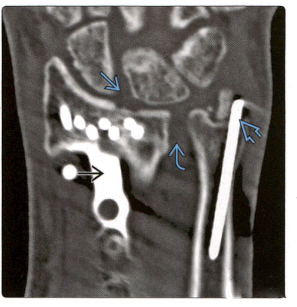

2. Реконструированная КТ показала: Т-образная пластина на ладонной стороне, стабилизирующая заживление перелома дистального отдела лучевой кости. Спицы Киршнера защищают перелом шиловидного отростка локтевой кости, но отмечают увеличение ладьевидно-полулунной перегородки и нижней щели лучелоктевого сустава, что указывает на повреждение связок.